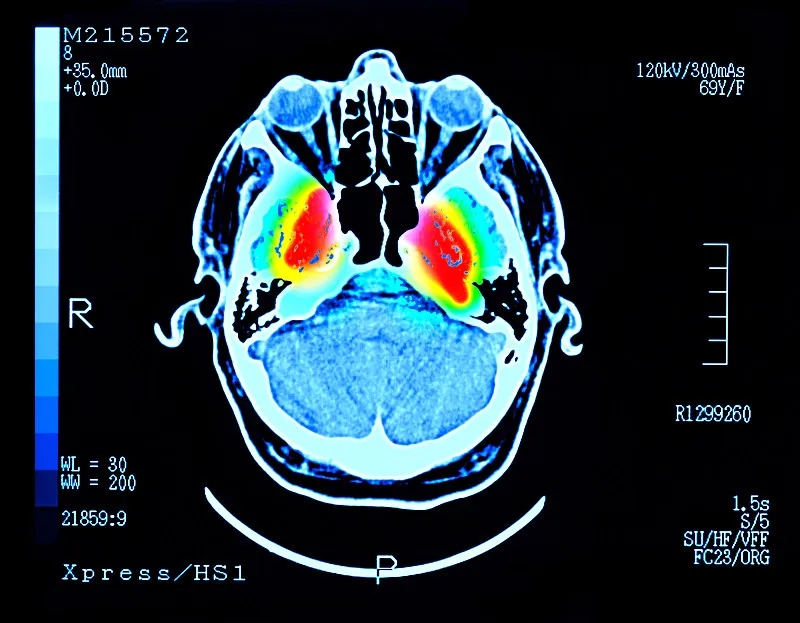

帕金森病 (PD) 是大腦中的一種疾病,它會殺死產生一種叫做“多巴胺”的化學物質的神經元。多巴胺是一種重要的化學物質,負責大腦內神經元之間的交流。細胞死亡主要發生在“黑質”,這是大腦中主要的多巴胺產生區域。

這些治療可緩解帕金森病的癥狀,但不會減緩或逆轉大腦神經細胞的損傷。隨著時間的推移,盡管進行了治療,但臨床特征會變得更糟。當患者被診斷出患有帕金森癥時,他們通常已經患病多年,并且黑質內的多巴胺細胞已經丟失了一半以上。早期檢測帕金森癥的測試可能有所幫助,但科學家們正在尋找一種方法來替換受損的細胞。